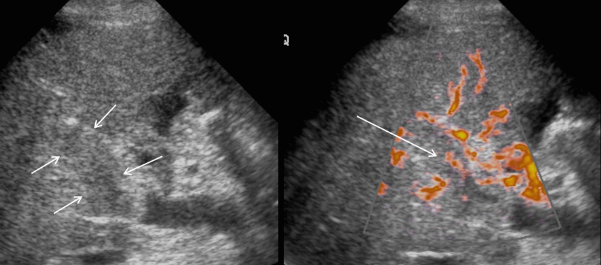

US finding

- 동일한 크기의 다발성 종괴가 나타난다.

- 고에코의 다발성 종괴: 대장암이 많으나 위암도 비교적 흔하다.

- 저에코의 다발성 종괴: 유방암, 폐암등에서 나타난다.

- 석회화나 내부 낭성 변성은 전이성 간종양을 시사하는 소견이다.

- bull's eys sign (종양 변연에 중심부가 고에코이고 경계부가 저에코인 두꺼운 띠가 보인다)

- cluster sign (종양이 융합하여 분엽모양을 이루어 마치 포도송이 모양을 나타낸다)